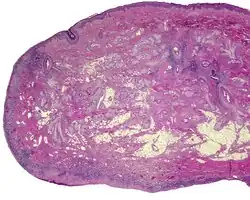

The lesions presents as a nodule or papule, either sessile or pedunculated. They may be soft or have a cartilaginous structure. By histologic examination, it is a recapitulation of normal external auricle. There will be skin, cartilaginous structures, and cartilage (although the last is not seen in all variants of this disorder).[4][5] Some investigators believe that the tragus is the only hillock which is derived from the first branchial arch. This is clearly suggestive that true cases of accessory auricle represent a true duplication of the hillocks that were part of the second branchial arch.[6] The second ear appears as a mirror image folded forward and lying on the posterior cheek.